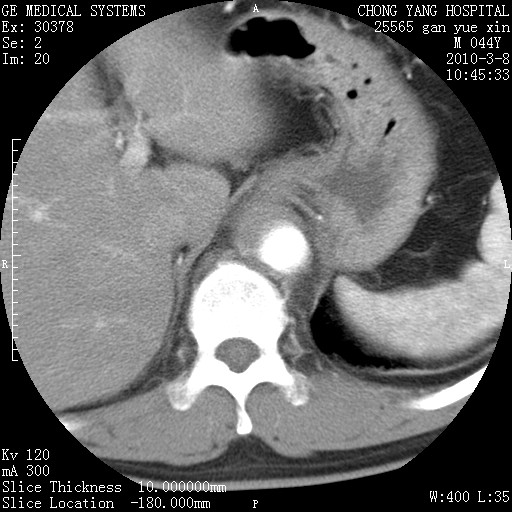

标题: CT24940:主动脉增强,典型病例。 [打印本页]

标题: CT24940:主动脉增强,典型病例。

夹层动脉瘤。

动脉夹层

夹层动脉瘤,典型

主动脉夹层。

动脉夹层的分型:

⒈debakey分型:根据主动脉夹层累及部位,分为三型:ⅰ型:原发破口位于升主动脉或主动脉弓部,夹层累及升主动脉、主动脉弓部、胸主动脉、腹主动脉大部或全部,少数可累及髂动脉。ⅱ型:原发破口位于升主动脉,夹层累及升主动脉,少数可累及部分主动脉弓。ⅲ型:原发破口位于左锁骨下动脉开口远端,根据夹层累及范围又分为ⅲa,ⅲb。ⅲa型:夹层累及胸主动脉。ⅲb型:夹层累及升主动脉、腹主动脉大部或全部。少数可累及髂动脉。

⒉stanford分型:a型:夹层累及升主动脉,无论远端范围如何。b型:夹层累及左锁骨下动脉开口以远的降主动脉。

夹层动脉瘤,少量胸水

夹层动脉瘤;左侧少量胸腔积液。